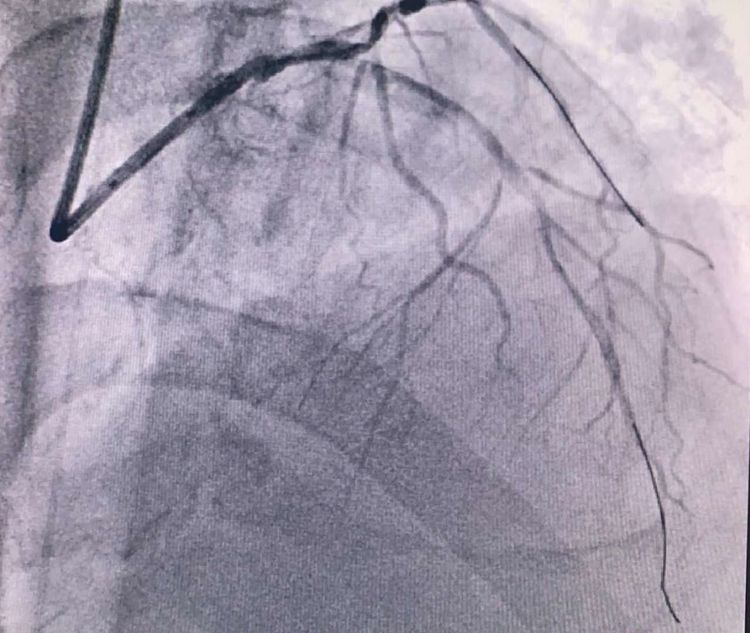

患者71岁高龄,外地医保患者。无高血压、糖尿病、吸烟病史。突发胸痛2小时急诊来院,病情就是命令。接到电话,立即启动我院的胸痛绿色通道,绕行CCU直达导管室。二线手术医生李妮妮责任总和冯韩章责任总,立即上台,给患者行冠脉造影。

患者前降支、右冠100%闭塞,LCX中段60%狭窄。命悬一线,手术台上持续胸痛。和患者家属及时沟通后,决定行PTCA术。血压低至60/40mmHg,在主动脉内球囊反博的支持下紧急行PCI术。轨道很快建立,导丝也及时通过病变血管,噩梦来了,患者发生室颤了。在吴栋梁院长的指挥下,李阳主任和心脏团队的成员共同努力下,除颤、冠脉内溶栓、多个球囊轮流上阵,患者病情平稳了,罪犯血管及时开通,血流恢复三级血流。平安下台,准备择日再处理冠脉情况。